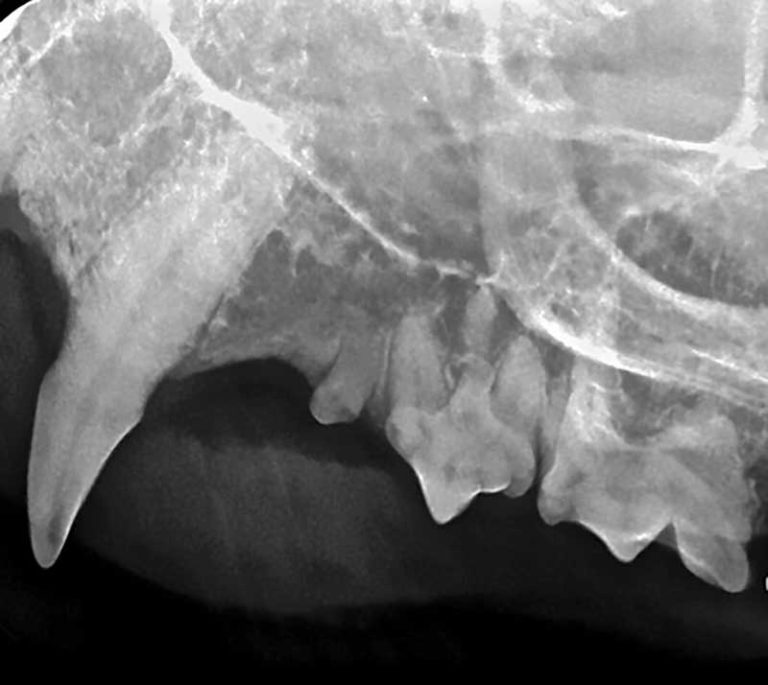

From www.veterinarypracticenews.com

Why your practice needs dental radiography Dental Radiographs Are Not Used For After reviewing published studies on radiography, the expert panel determined lead aprons and thyroid collars are not necessary to. Which is not a use for panoramic radiographs in dentistry? Diagnosis of decay, periodontal disease, or periapical. Click the card to flip ๐. Dental radiographs are a useful and necessary tool in the diagnosis and treatment of oral diseases such as. Dental Radiographs Are Not Used For.